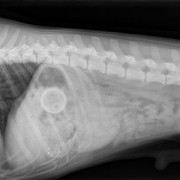

Snuf wordt verdoofd en de dierenarts opent de buik

De blaas wordt opgezocht en geopend

En daar is de eerste steen...

Close up

De boosdoeners